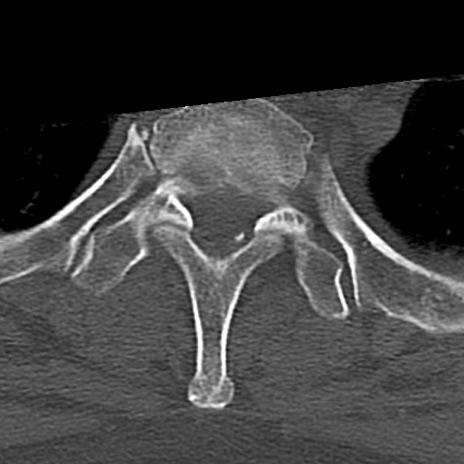

頚椎CT

横断像